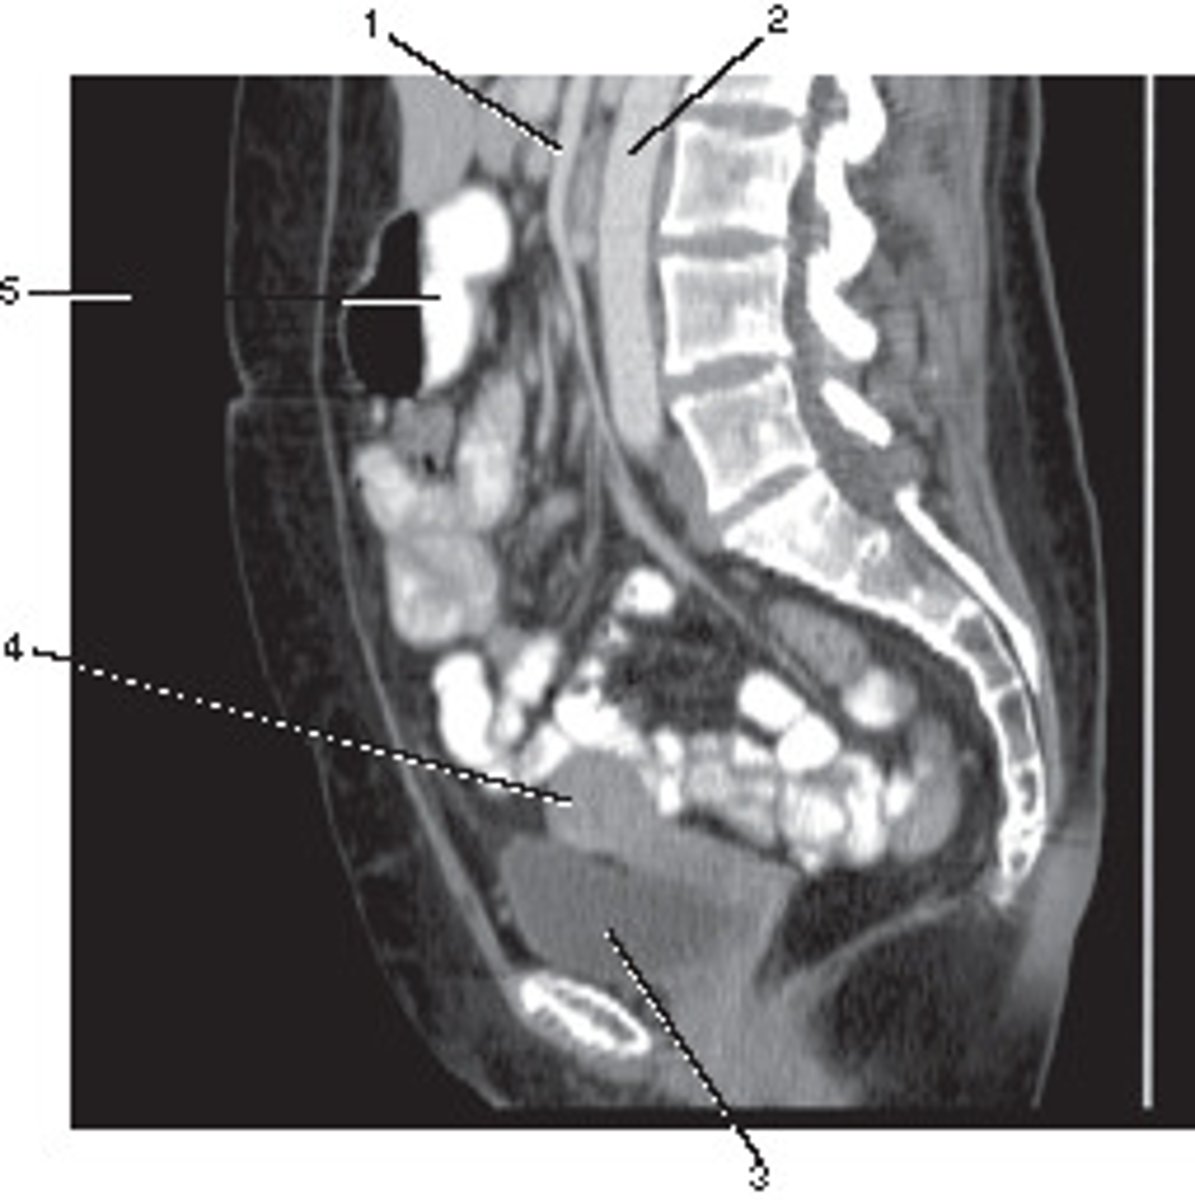

Sagittal

What anatomic plane best describes this image

<p>What anatomic plane best describes this image</p>

Uterus

Number 4 corresponds to which of the following?

<p>Number 4 corresponds to which of the following?</p>